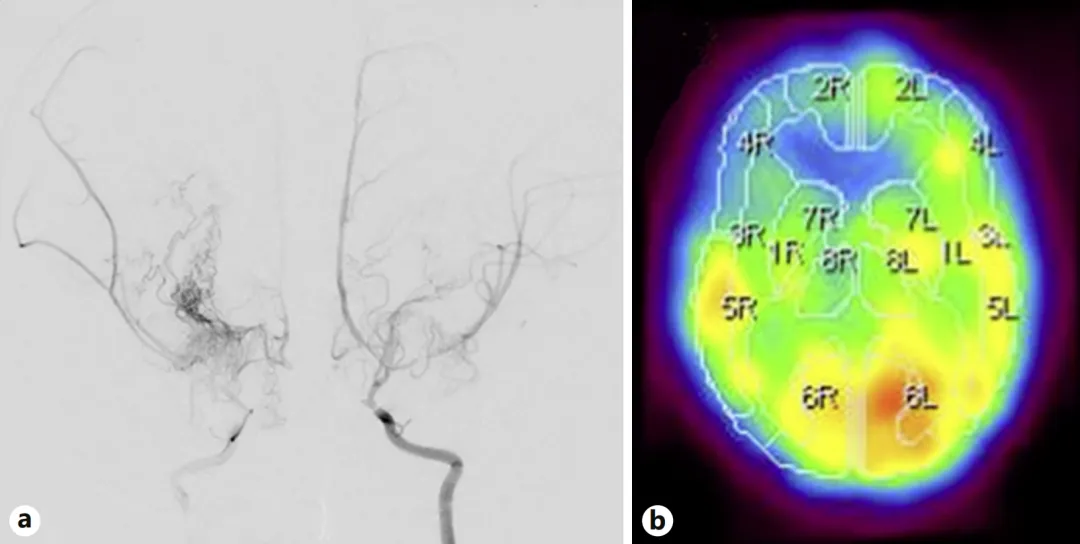

2岁女性患儿突发摔倒症状,随后出现突发性抽搐,检查确诊:烟雾病合并脑梗死,双侧颈内动脉严重狭窄,以及右额叶脑血流显著减少。

图a显示类似三条主干道同时堵塞,脑组织处于"缺氧"边缘挣扎状态。

图b解释患儿反复猝倒原因:大脑缺血时身体突然失去肌张力控制。

图a:二次术后半年,双侧颈内动脉血管造影显示侧支血管网络发育良好,基底烟雾血管消退。

图b:双侧脑血流显示改善征象。